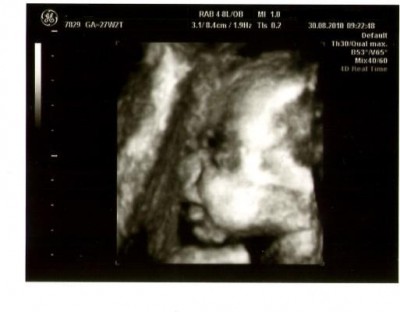

So und jetzt mal ein Bildchen von unserer Kleinen.

nein, Leo, das ist ja ein supersüßes Bild...